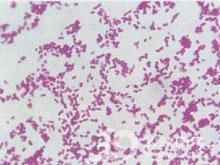

實驗室:白細胞總數正常或增多,中性粒細胞數增加.經防污染採樣技術獲得的痰標本,診斷價值較大。痰塗片發現革蘭陰性球桿菌可成為診斷的重要線索。